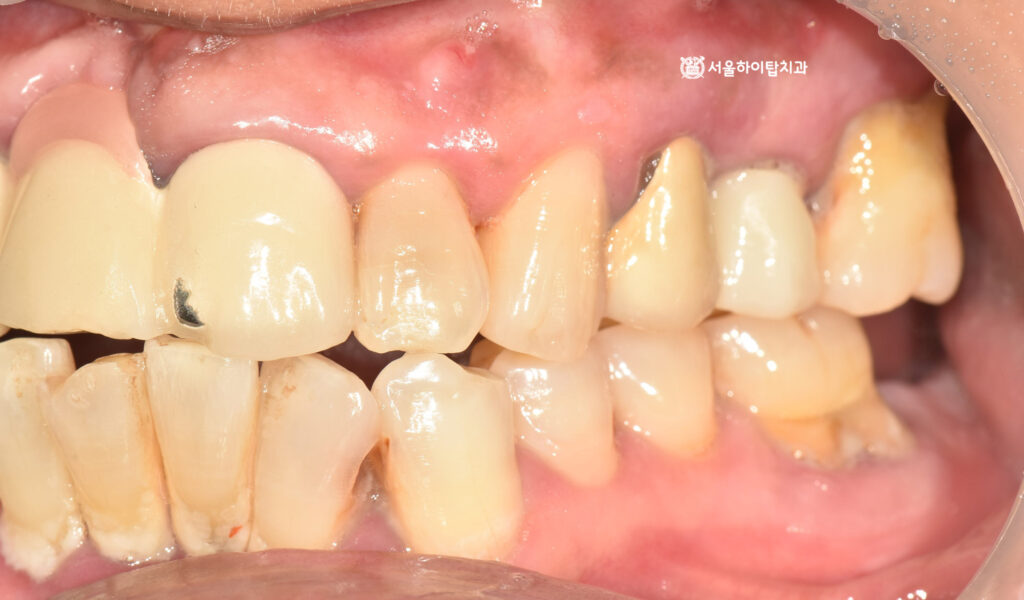

구강 내 사진을 보면,

곳곳에 심한 치석과 치태가

쌓여 있는 모습이 확인됩니다.

주변 잇몸도 붉게 변해 있는 것을 볼 수 있어,

전형적인 치주염의 소견으로 볼 수 있습니다.